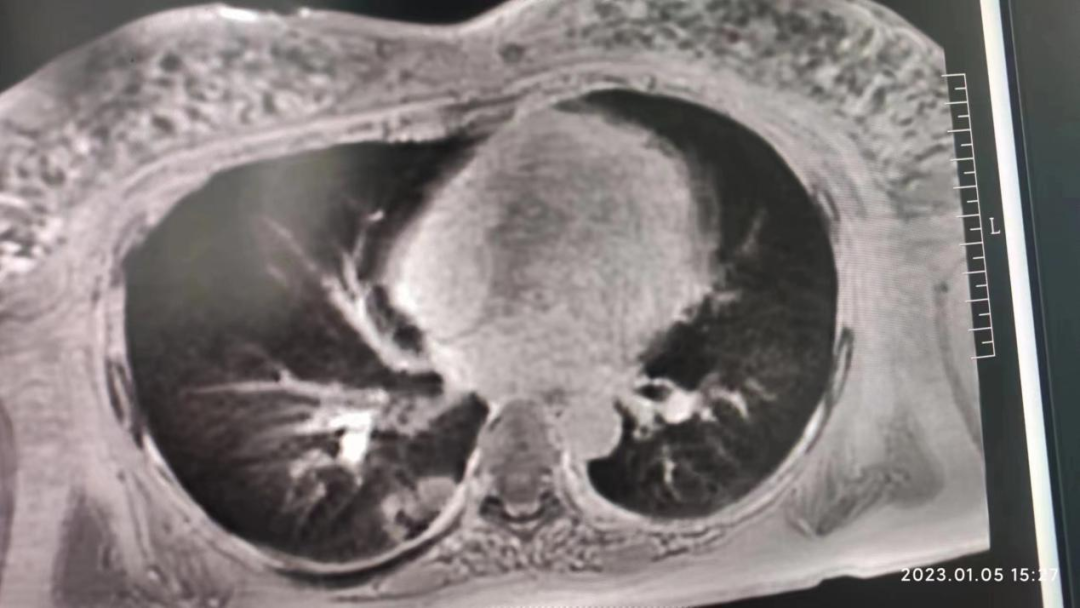

此外,联影智能光梭uMR790 3.0T 磁共振具有丰富的扫描检查模式,能够完成包括神经系统、胸部、腹部、盆腔、心血管、骨骼关节、软组织、乳腺等全身各部位磁共振检查,并且能够完成以前不能进行的胸部等部位磁共振检查。不同序列能够对组织结构和病灶进行多角度、多方位观察,利于病灶定性分析,同时,能够大大提高较多、较小病灶的检出率,做到早发现、早治疗、提升患者后续生活质量。并且可以大量应用于全身各部位的功能成像,能够详细地观察人体各器官结构和病变的形态学变化,有利于疾病的诊断和鉴别诊断。

联影磁共振怎么样开启高精度诊断新模式!联影光梭3.0T磁共振落户周口市中心医院_https://www.jmylbn.com_新闻资讯_第9张

(胸部MRI成像)

周口市中心医院磁共振室现已全面开展各项磁共振高级功能成像(包括SWI、PWI、BOLD、MRS、DTI等)、胎儿、乳腺、心脏、颞颌关节、动脉高分辨血管壁分析以及周围神经等检查,陆续开展磁共振介入和磁共振高级科研临床应用。磁共振功能成像广泛应用于临床各科,如神经内外科、肝胆内外科、心内科、小儿科、妇产科、泌尿科、肿瘤内外科等临床各个学科,这些极其优秀的特色MR成像技术,大大提高临床疑难疾病的诊断符合率,更有助于临床医生更准确有效及时的治疗,让患者得到更优质的康复。比如,DTI用于脑肿瘤对正常白质纤维束的侵占,术前和术后对于治疗效果的评估,可以更准确地反映白质纤维束的空间走向。在心血管领域突破了心脏禁区,可全面评估,心脏大血管解剖结构成像、心肌功能分析等全方位的检查研究,大大方便了中老年心脏病患者。在体部领域实现了肝脏三维容积超快速多期动态增强检查,可以敏感发现早期微小肝癌,不会遗漏边缘部位和微小病变。充分利用GE 3TMR“乳腺微观成像”高分辨展示乳腺结节、导管及淋巴结转移;“磁共振灌注成像”界定急性脑梗塞的缺血半暗带;“波谱成像”能真正在活体(病人)上分析化学成分。因此,努力提升MRS、SWI、DTI、PWI、CEMRA、腹部MR平扫及增强等MR功能成像业务,极大程度地避免了病人要到外地就医问题,也进一步提升了科室技术水平,并能获得良好的社会效益和经济效益。MR引导下穿刺活检及介入治疗。